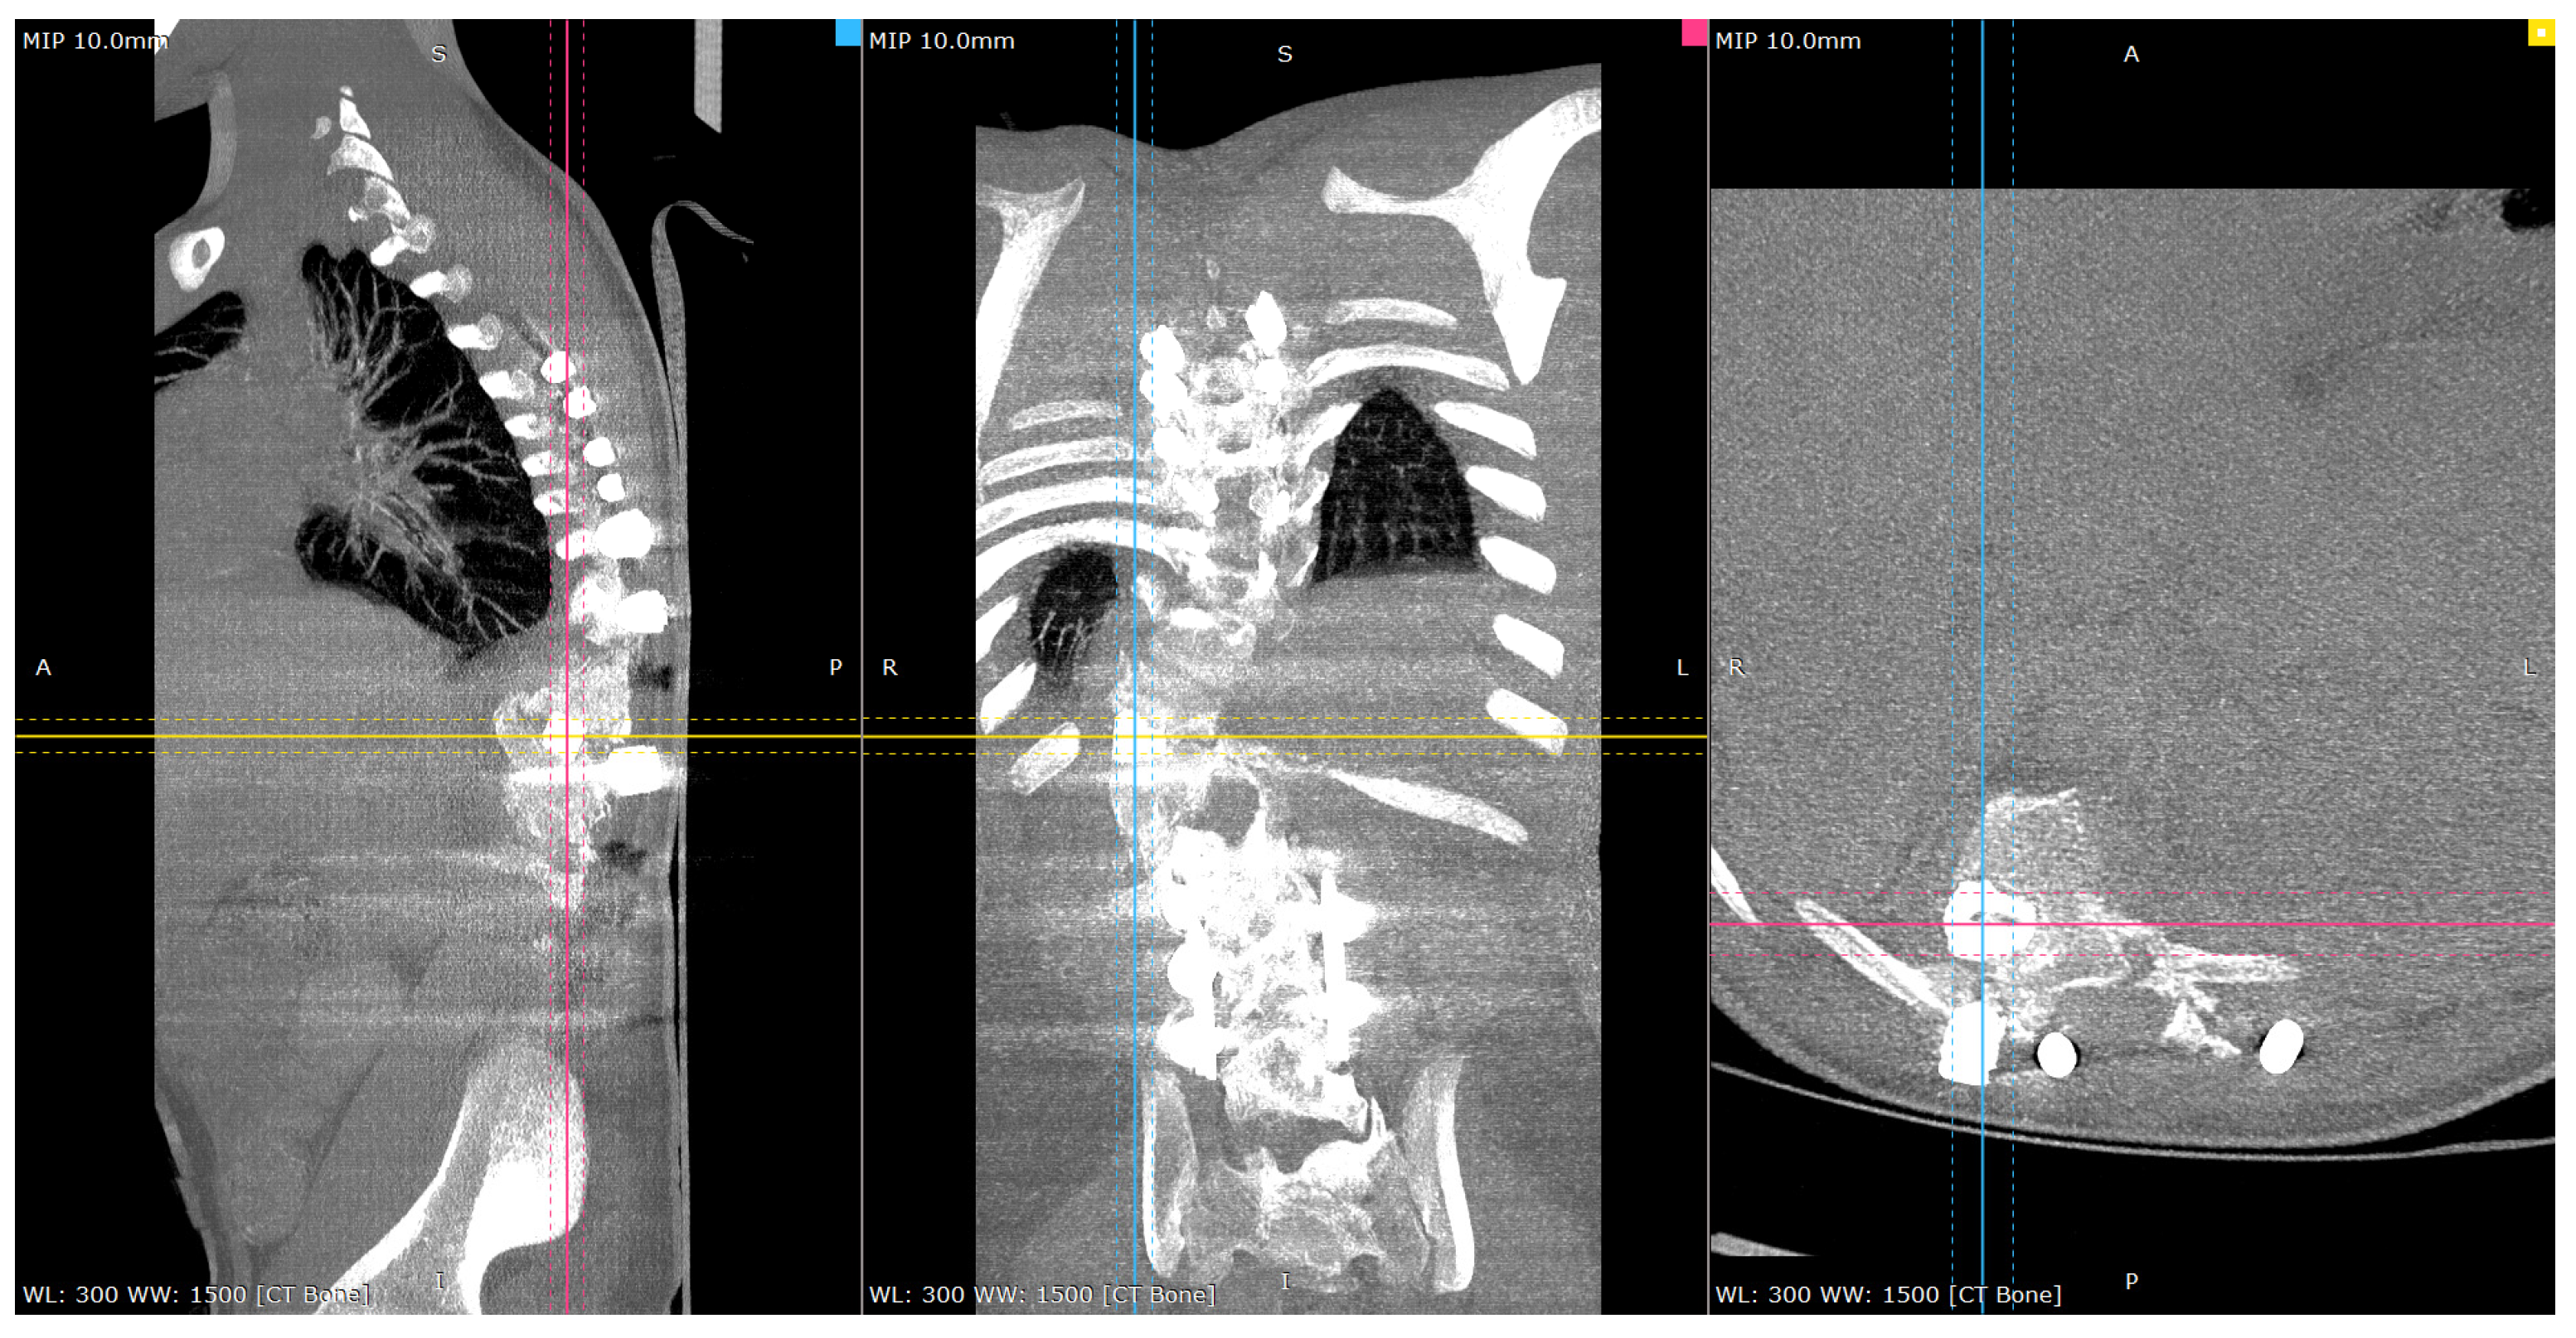

Postoperative CT scan images verified bone formation across the congenital defect, and clinically, he was balanced in both sagittal and coronal planes (Figure 9, Figure 10, Figure 11 and Figure 12).

Figure 10.

Representative post-op CT scan views—4-months Post-operatively. Cross-reference grid lines mark the intersection of the corresponding image planes: Blue—sagittal; Pink—Coronal; Yellow—Axial view.